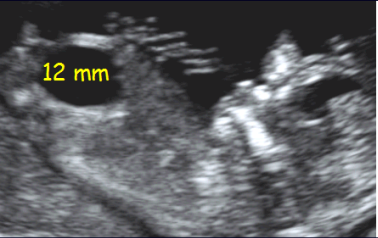

Diagnóstico ultrassonográfico:

- A cisterna magna é > 10mm no corte cerebelar transverso.

- Vermis: normal.

- Diagnóstico diferencial: Cisto da Bolsa de Blake (expansão do 4o ventrículo em direção à cisterna resultando em cisto avascular, unilocular na fossa posterior; vermis normal deslocado superiormente), cisto aracnoide (cisto na cisterna magna com efeito de massa nas estruturas adjacentes; vermis normal).